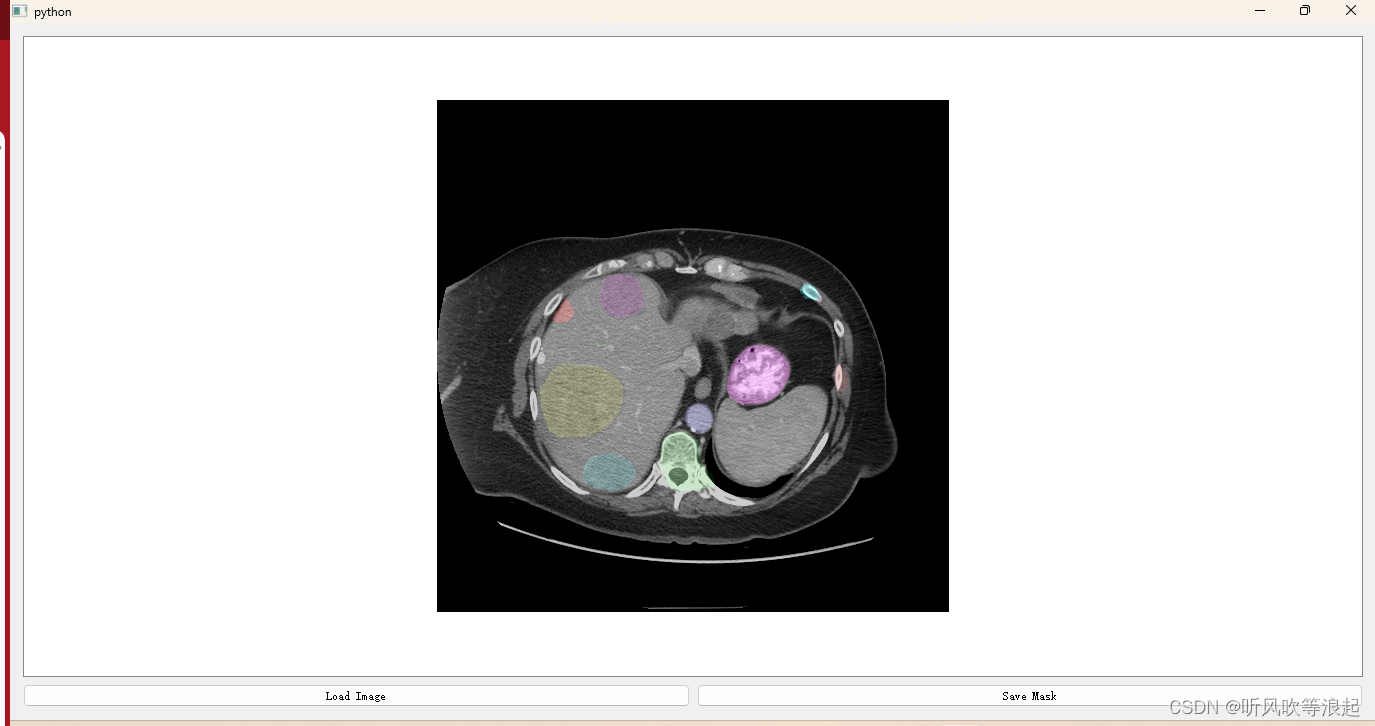

pip install PyQt5因为bbox很难指定,官方给出了GUI界面。类似于labelimg那种鼠标绘制边界框,即可推理指定的区域,这样方便推理

展示如下: